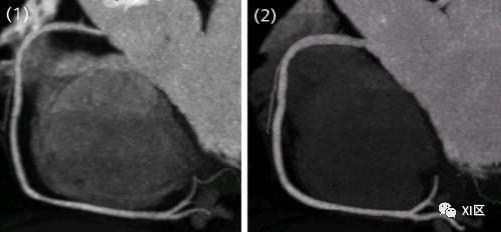

一些研究甚至发现,如果不使用硝酸甘油进行的冠脉CTA检查,有可能出现误诊,如下图的几个病例。

A、 未经硝酸甘油注射的MSCT显示RCA无明显明显狭窄。B、 常规冠状动脉造影显示RCA近端(如箭头所示)存在明显的狭窄,未使用硝酸甘油的MSCT未能发现。